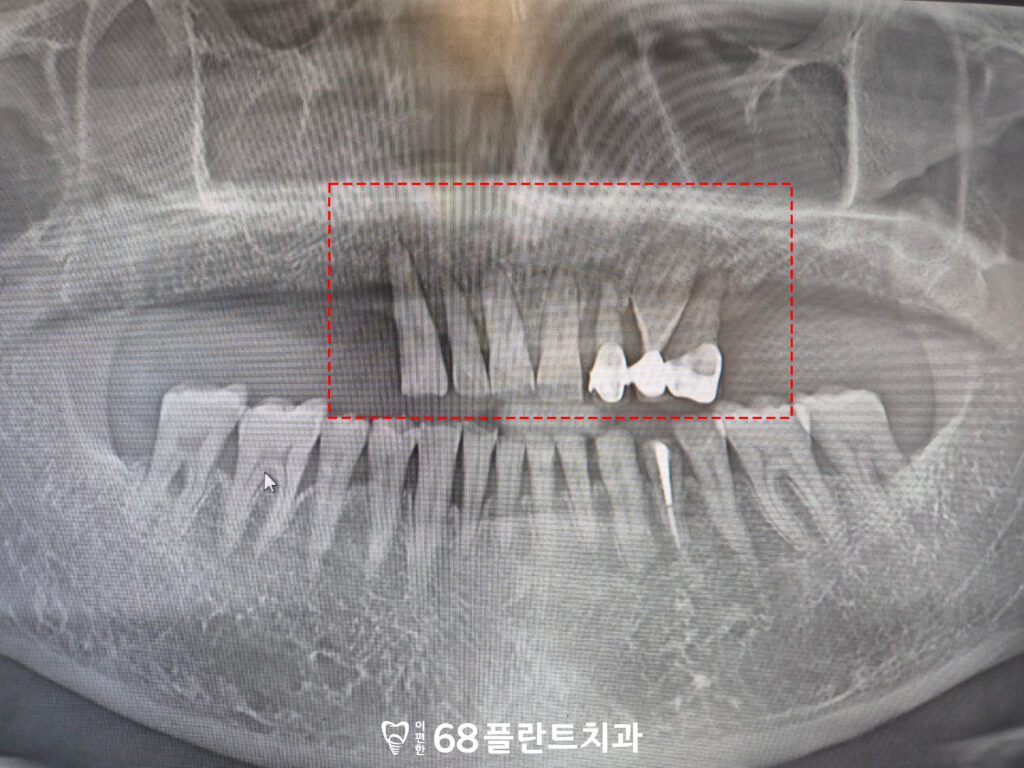

확인해 보니,

위쪽 어금니 양쪽이 전부

치아가 상실된 상태였으며

남아있는 앞니는

치주염으로 인해 잇몸뼈가 소실되어 있었습니다.

이로 인해, 치조골 지지가 충분하지 않아

저작 시 힘을 버티기 어려운 상황이었고

이미 염증이 반복되면서

예후 또한 좋지 않은 상태로 판단되었는데요.

그래서 본원에서는

위 치아 전부 발치 후

철산역임플란트를 통해

기능을 회복하기로 계획을 수립하였습니다.